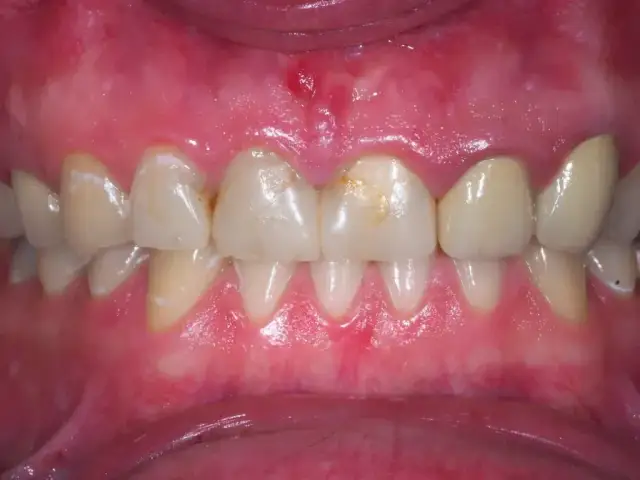

Czy zapalenie dziąseł jest zaraźliwe? Poznaj różnicę między przenoszeniem bakterii a chorobą. Dowiedz się, jak skutecznie chronić siebie i bliskich!

Opuchnięte dziąsła? Poznaj najczęstsze przyczyny, objawy i skuteczne metody leczenia. Sprawdź, jak sobie pomóc i kiedy iść do dentysty.

Opuchnięte dziąsła? Odkryj sprawdzone domowe sposoby na szybką ulgę i dowiedz się, kiedy konieczna jest wizyta u dentysty. Zadbaj o zdrowie jamy ustnej!